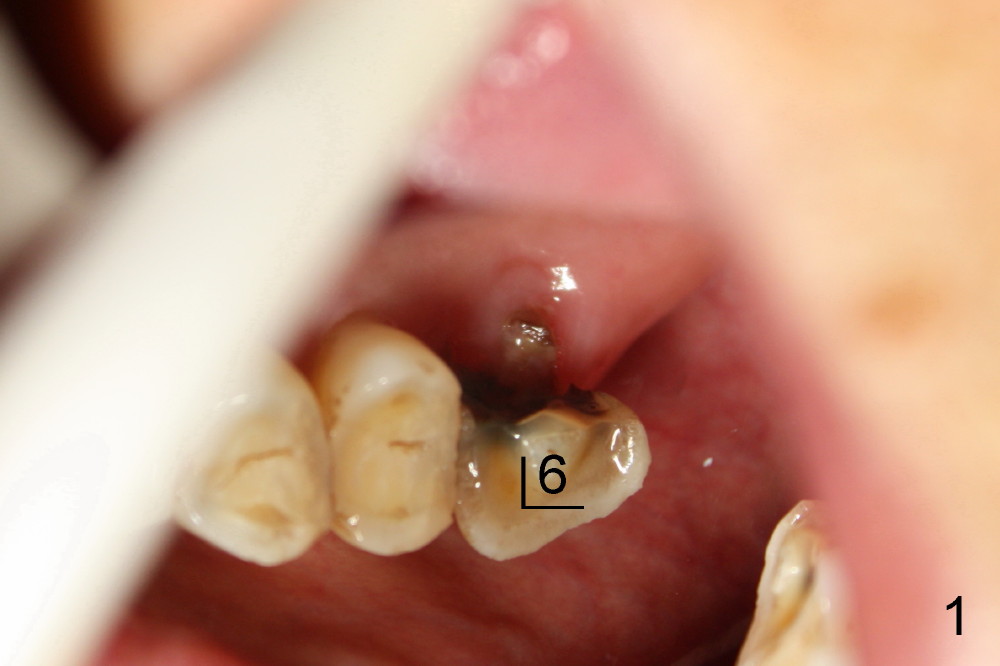

A 78-year-old lady has history of osteoporosis and history of taking Fosamax (Alendronate). Her upper left 1st molar needs extraction (Fig.1). The latter, appears to be easy, since the palatal root has lost. The remaining buccal roots have no bony support (Fig.2). Immediate implant should not produce extra trauma, leading to osteonecrosis.